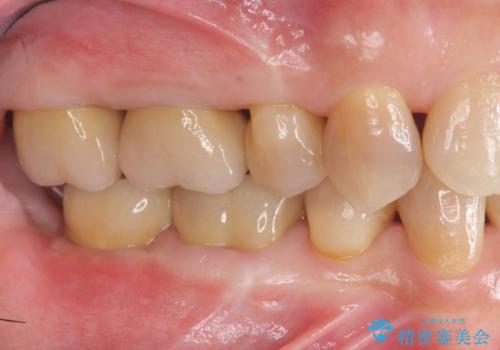

においやぐらつきなどの深い症状がなくなり、しっかりと噛めるようになった!と喜んでいただくことができました。